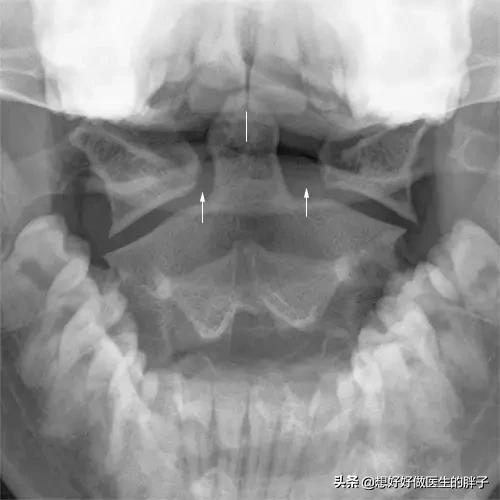

被験者の記述からすると、20年以上前から片頭痛の既往があり、現在、風池のツボ付近で痛みが出始めていることから、後頭下筋の問題であれば、筋の問題が顕著になってきている可能性がある。の初診をお勧めする。頚椎のX線フィルムまた、頸椎の湾曲異常の有無も確認することが望ましい。頚椎の口開けフィルム頚椎の解剖学的な異常、つまり鎖骨軸椎の異常の有無を明らかにするために、患者の状態を予備診断し、頚椎の問題の有無を観察することが可能である。